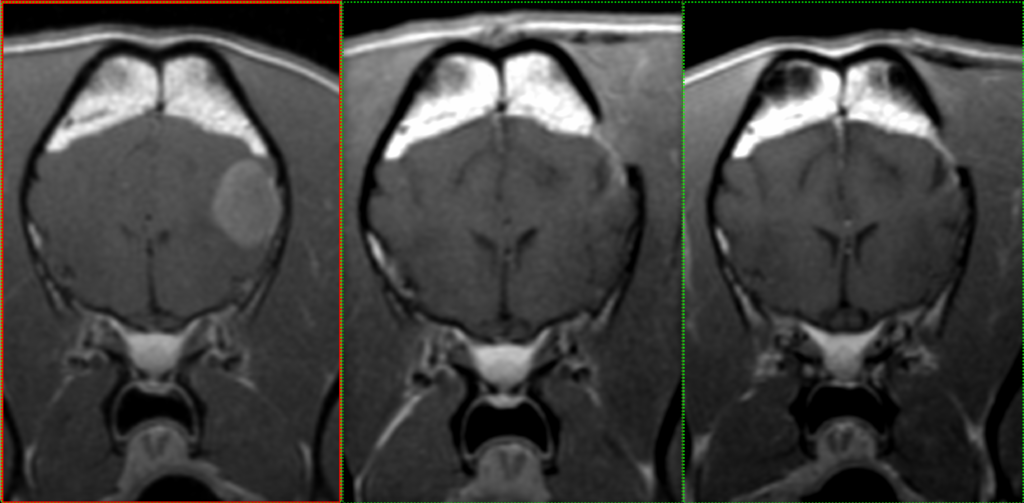

Initially, Rosie had a meningioma diagnosed in 2021. Following the diagnosis, Rosie had the tumour, which measured 1.5cm x 1.5cm, removed from her frontal lobe in December that year and has gone from strength-to-strength following the operation.

“Rosie has had follow up MRI scans and after 18 months there is no sign of it regrowing so we appear to have removed all of it. It’s a great result for Rosie and her owners.